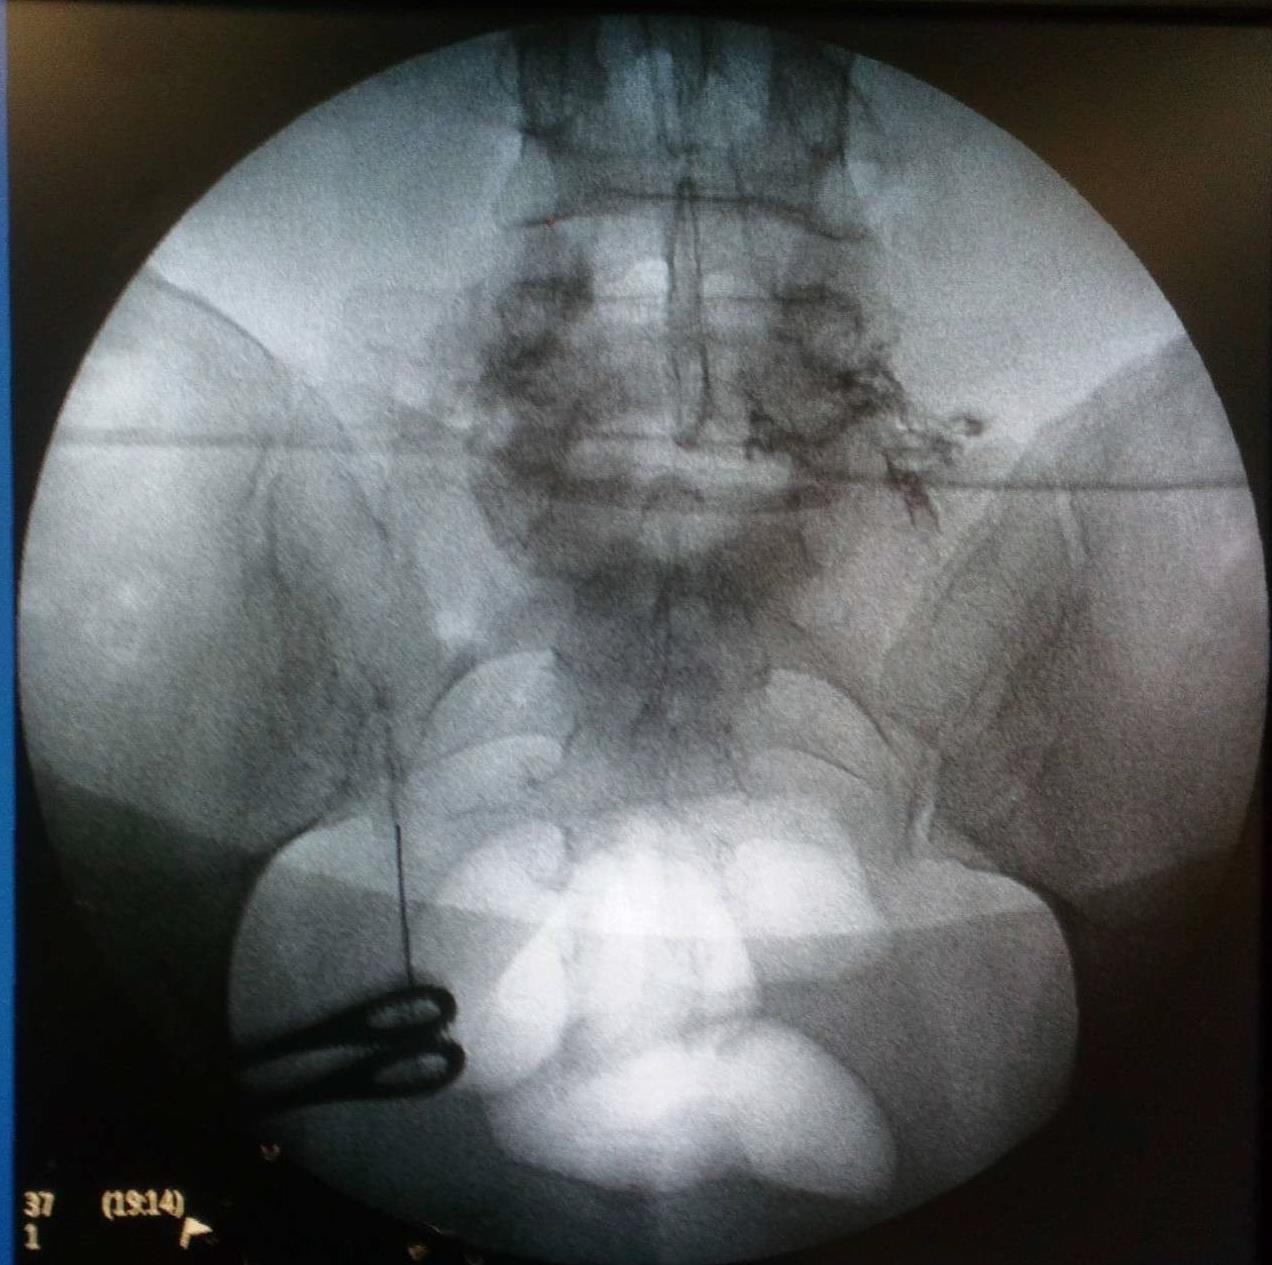

Ασθενής με 2 δισκοκήλες

Aσθενής 35 ετών με έντονο άλγος οσφύος από 4μήνου και αντανάκλαση στο κάτω άκρο λόγω 2 δισκοκηλών σε 2 επίπεδα. Με τοπική αναισθησία τοποθέτηση 2 βελόνων στα σημεία πίεσης των νεύρων. Έλεγχος σωστής τοποθέτησης με χρήση σκιαστικού και εισαγωγή μείγματος αναλγητικών. Άμεση ανακούφιση με αποτέλεσμα που διατηρείται 6 μήνες μετά.